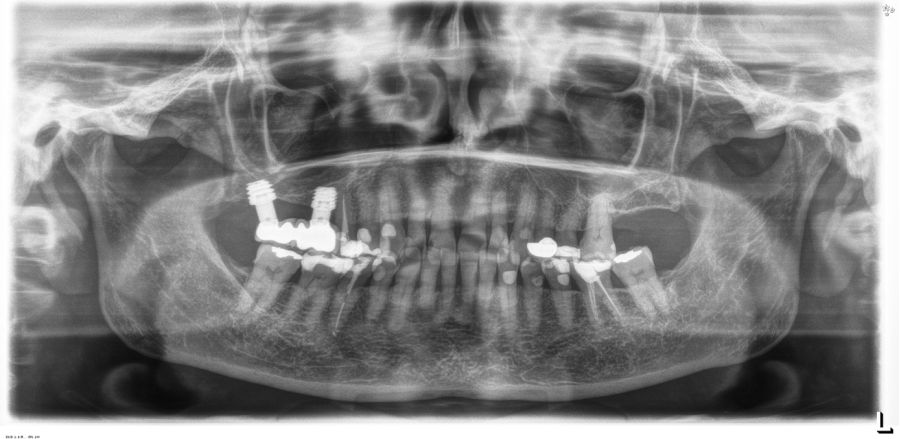

La inserción de los implantes fue realizada por un mismo cirujano, mediante la técnica de fresado biológico, a bajas revoluciones, sin irrigación. Con esta técnica todo el hueso recolectado es embebido en PRGF-Endoret durante la cirugía para posteriormente ser utilizado como injerto óseo particulado17-19. El fresado final de la cortical sinusal se realizó con la fresa de corte frontal (ideada para esta técnica) que permite la retirada del suelo del seno maxilar sin dañar la membrana de Schneider6-7. Una vez la membrana es accesible mediante la perforación crestal, se despega, se inserta el implante con el motor quirúrgico fijado a 25 Ncm y 25 rpm finalizando la inserción del implante con la llave dinamométrica (Figura 1). El implante eleva lentamente la membrana a la vez que es insertado en el neo-alveolo.

Una vez finalizada la cirugía se realiza una radiografía periapical con paralelizador, que se utilizó como punto de partida. Los pacientes acudieron posteriormente para la realización nuevas radiografías de control, tomadas con la misma técnica y sobre las que se realizaron las mediciones necesarias para comprobar la estabilidad y pérdida ósea crestal de los implantes. La medición de la pérdida ósea marginal se realizó en la última radiografía periapical realizada con posicionador de seguimiento. Una vez obtenida la radiografía en formato digital es calibrada mediante un software específico (ImageJ software- Rasband, W.S., ImageJ, U. S. National Institutes of Health, Bethesda, Maryland, USA, https://imagej.net/ij/, 1997-2018) a través de una longitud conocida en la radiografía como es el implante dental. Una vez se introdujo la medida de calibración, el programa informático realiza un cálculo basado en esta medida para eliminar la magnificación, pudiendo realizar mediciones lineales exentas de este error (Figura 2). La pérdida ósea de los implantes fue medida en dos puntos: mesial y distal en cada uno de los casos (Figura 3).

Fueron reclutados 13 pacientes que cumplieron los criterios de inclusión en los que se insertaron 30 implantes. La edad media fue de 70 +/- 1 años en el momento de la cirugía y 10 de los pacientes fueron hombres. El tiempo medio de seguimiento desde la carga fue de 126 meses (+/- 1,79; Rango 120- 150 meses). Los diámetros, longitudes y posiciones de los implantes se muestran en la Figura 4. La altura media de la cresta residual fue de 4,86 mm (+/-0,97; rango 1,95-5,88 mm). El torque de inserción medio de los implantes fue de 26,45 Ncm (+/- 1,89). Una vez insertados y cargados los implantes, la altura media final fue de 9,68 mm (+/- 2,66; rango 6,74-13,11 mm), lo que supone una ganancia promedio de 5 mm. A los 10 años, se observa una disminución media de la altura ósea ganada en los implantes en conjunto de 0, 29 mm (+/- 0,77).

La media de la pérdida ósea mesial fue de 0,73 mm (+/- 0,75 mm) y la media de la pérdida ósea distal fue de 0,98 mm (+/- 1,2 mm). No existió ningún fracaso en los implantes estudiados, por lo que la supervivencia fue del 100%. Todas las prótesis se rehabilitaron de forma atornillada mediante transepitelial, siendo un 85% de ellas puentes de 2 a 4 unidades y el resto prótesis completas. No se produjeron complicaciones en la técnica quirúrgica en ninguno de los casos estudiados, sin producirse ninguna perforación de la membrana de Schneider.

En las Figuras 5-16 se muestra uno de los casos incluidos en el estudio.